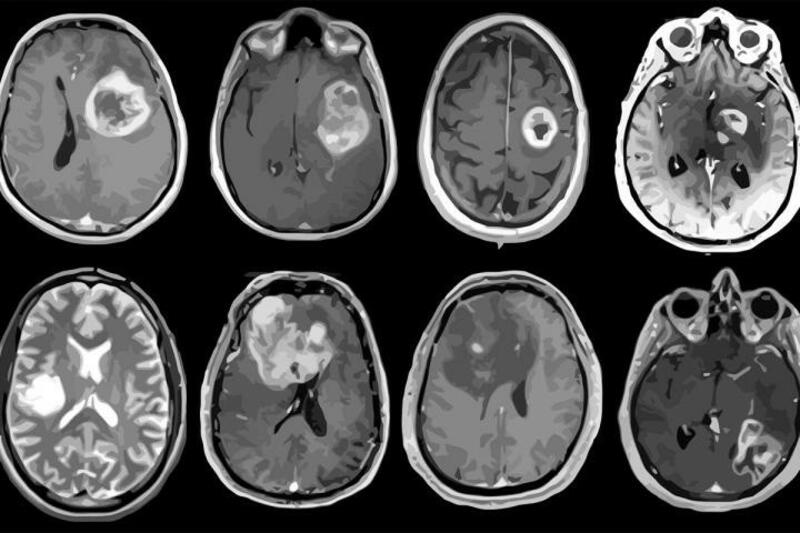

Desde la SEN advierten de que, este tipo de tumores que aglutinan más de 120 tipos en el sistema nervioso, en los últimos años se ha observado un incremento en el número de casos por año debido, principalmente, a la mejora de las técnicas de imagen -lo que ha permitido perfeccionar su diagnóstico-, y al progresivo envejecimiento de la población.

Y es que la edad de aparición de los tumores cerebrales presenta un pico en la edad pediátrica, pero también un aumento progresivo con la edad en adultos, hasta alcanzar su máximo de incidencia entre la sexta y la séptima década de la vida. Se estima que, en la actualidad, en España hay alrededor de 20.000 personas que padecen algún tipo de tumor cerebral, clasificado bien como un tumor primario (originado en el cerebro) o como un tumor metastásico (originado en otras partes del cuerpo, pero que se ha diseminado al cerebro).

Los tumores cerebrales suponen aproximadamente el 2% de todos los cánceres diagnosticados en adultos y el 15% de los diagnosticados en niños, lo que le convierte, durante la edad pediátrica, en el segundo tipo de cáncer más detectado después de la leucemia. En todo caso, aunque no son los tumores más frecuentes, tienen un alto impacto en la vida de las personas que los padecen.